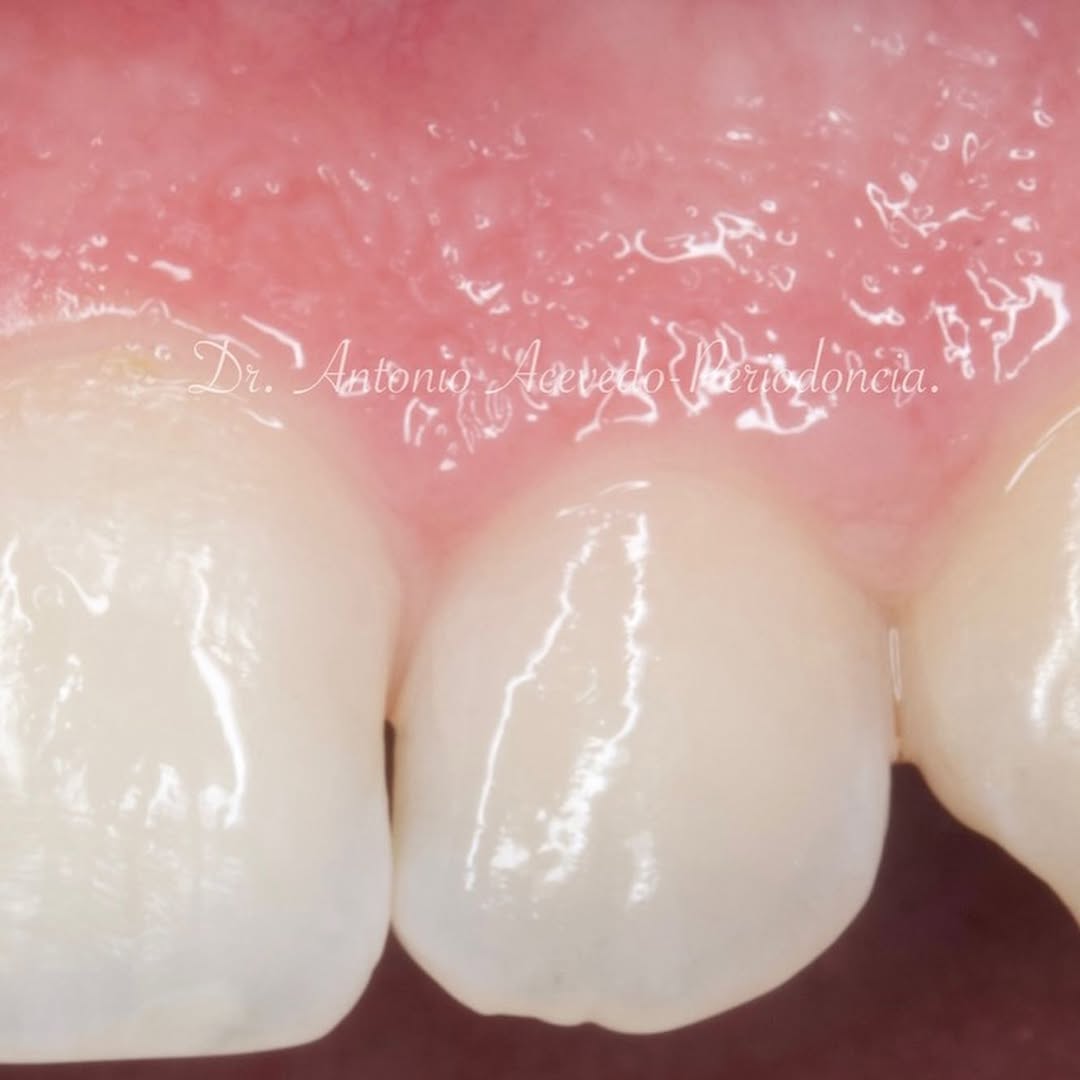

Durante una mañana, asistirás a una Cirugía Mucogingival de recubrimiento radicular de una recesión unitaria en 31 con frenillo asociado. Gracias al uso del microscopio y a la proyección en tiempo real en pantalla, verás exactamente lo mismo que veo yo durante la cirugía, sin tener que estar